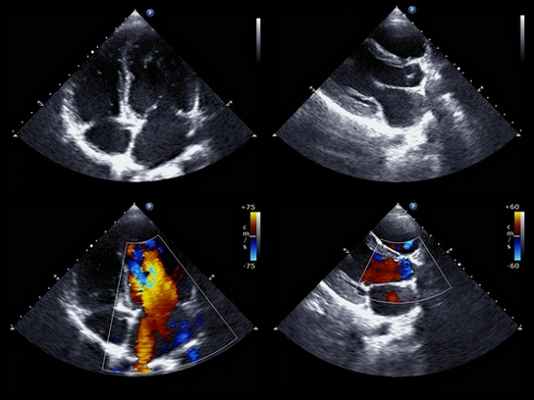

Следует подозревать неинфекционный эндокардит в том случае, если у больных с хроническими заболеваниями развиваются симптомы, соответствующие артериальной эмболии. Должны быть выполнены серия посевов крови и Культуральное исследование Тест-культура – рост микробов на питательной твердой или жидкой среде; увеличение числа организмов упрощает идентификацию. Культура также облегчает тестирование антибактериальной восприимчивости. Прочитайте дополнительные сведения эхокардиография Эхокардиография На данном фото изображен пациент, которому выполняется эхокардиография. На этом изображении показаны все 4 камеры сердца, а также трикупсидальный и митральный клапаны. Эхокардиография использует. Прочитайте дополнительные сведенияДифференциальная диагностика с культурально-отрицательным инфекционным эндокардитом представляет трудности, но очень важна. Применение антикоагулянтов часто показано при неинфекционном эндокардите, но противопоказано при инфекционном эндокардите. Необходимо провести анализ на наличие антиядерных антител и антифосфолипидного синдрома.

Оценка с помощью эхокардиографии и исключение инфекционного эндокардита с помощью посевов крови.

Основные методы при постановке диагноза — это бактериологический анализ (посев) крови и ультразвуковое исследование сердца (эхокардиография).

Эхокардиография позволяет подтвердить или исключить наличие отложений на эндокарде и клапанах, абсцесс или недостаточность клапанов. В некоторых случаях дополнительно назначают так называемую чреспищеводную эхокардиографию. В процессе обследования больному через пищевод вводят гибкую трубку вплоть до уровня сердца. Комбинация обоих методов УЗИ позволяет с большой точностью определить изменения во внутренних структурах сердца.